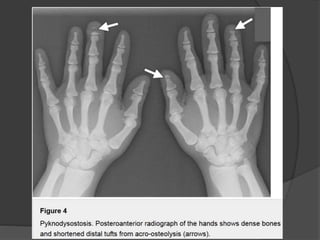

Pyknodysostosis

Patients with pyknodysostosis present with a complex of characteristic

features, including

• dwarfism

• pectus excavatum

• short fingers from acro-osteolysis

• hypoplasia of the facial bones, causing dysmorphic facial features.

Radiographically, there is generalized osteosclerosis similar to osteopetrosis,

but with preservation of the medullary canal of long bones.

Dense vertebral bodies with characteristic sparing of the transverse

processes is seen.